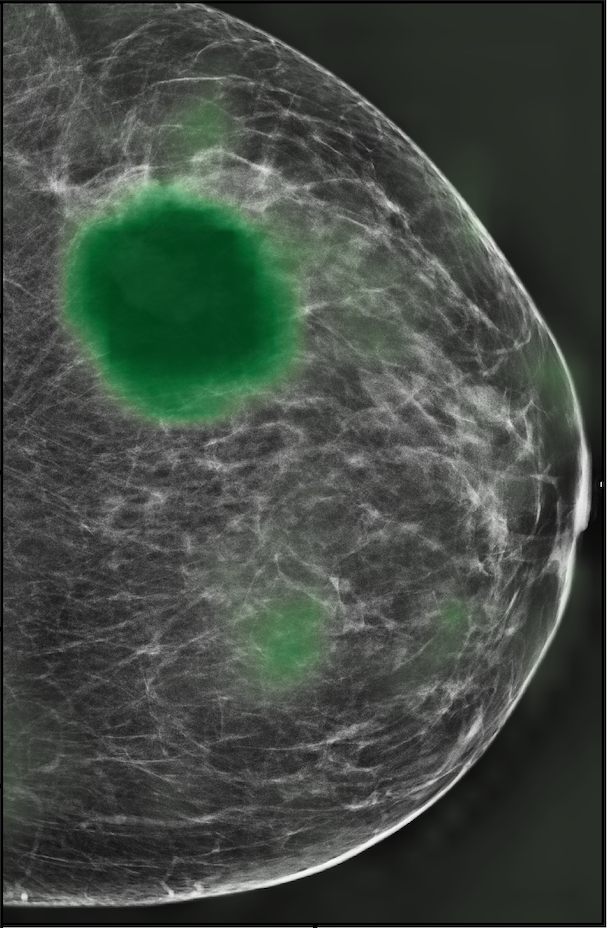

In Figure 7, we visualize saliency maps for four samples selected from the test set. In the first two examples, the saliency maps are highly activated on the annotated lesions, suggesting that our model is able to detect suspicious lesions without pixel-level supervision. Moreover, the attention is highly concentrated on ROI patches that overlap with the annotated lesions. In the third example, the saliency map for benign findings identifies three abnormalities. Although only the top abnormality was escalated for biopsy and hence annotated by radiologists, the radiologist’s report confirms that the two non-biopsied findings have a high probability of benignity and a low probability of malignancy. In the fourth example, we illustrate a case when there is some level of disagreement between our model and the annotation in the dataset. The malignancy saliency map only highlights part of a large malignant lesion with segmental coarse heterogeneous calcifications. This behavior is related to the design of : a fixed pooling threshold cannot be optimal for all sizes of ROI. The impact of is further studied in 3.6. This example also illustrates that while human experts are asked to annotate the entire lesion, CNNs tend to emphasize only the most informative regions. While no benign lesion is present, the benign saliency map still highlights regions similar to that in the malignancy saliency map, but with a lower probability than the malignancy saliency map. In fact, calcifications with this morphology and distribution can also result from benign pathophysiology [42].